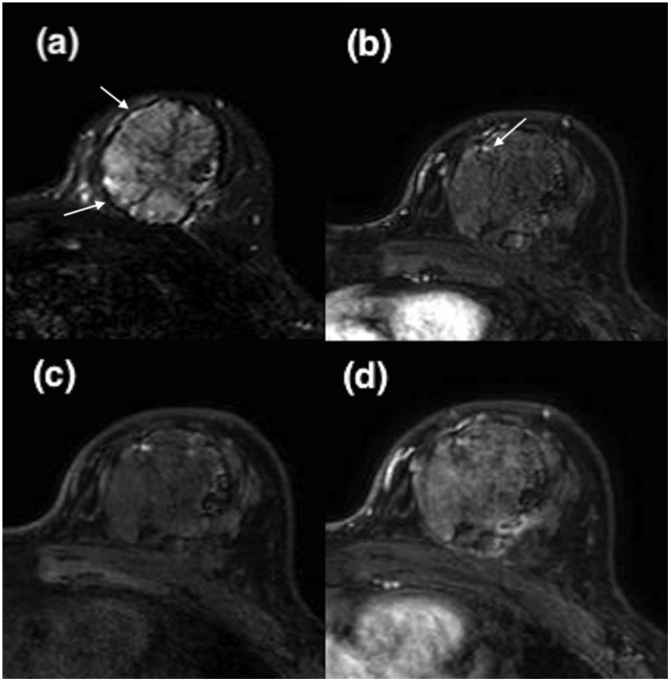

MRI images of the tumor after neoadjuvant chemotherapy.

(a) T2-weighted image, (b) non-contrasted T1-weighted image with fat saturation, (c)(d) gadolinium-enhanced T1-weighted image with fat saturation 20 s and 85 s after contrast media injection showing strong susceptibility artifact.